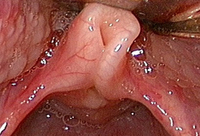

Laryngeal cleft

From the personal teaching collection of Simone J. Boardman, MBBS, FRACS (OHNS) and C. Martin Bailey, BSc, FRCS, FRCSEd